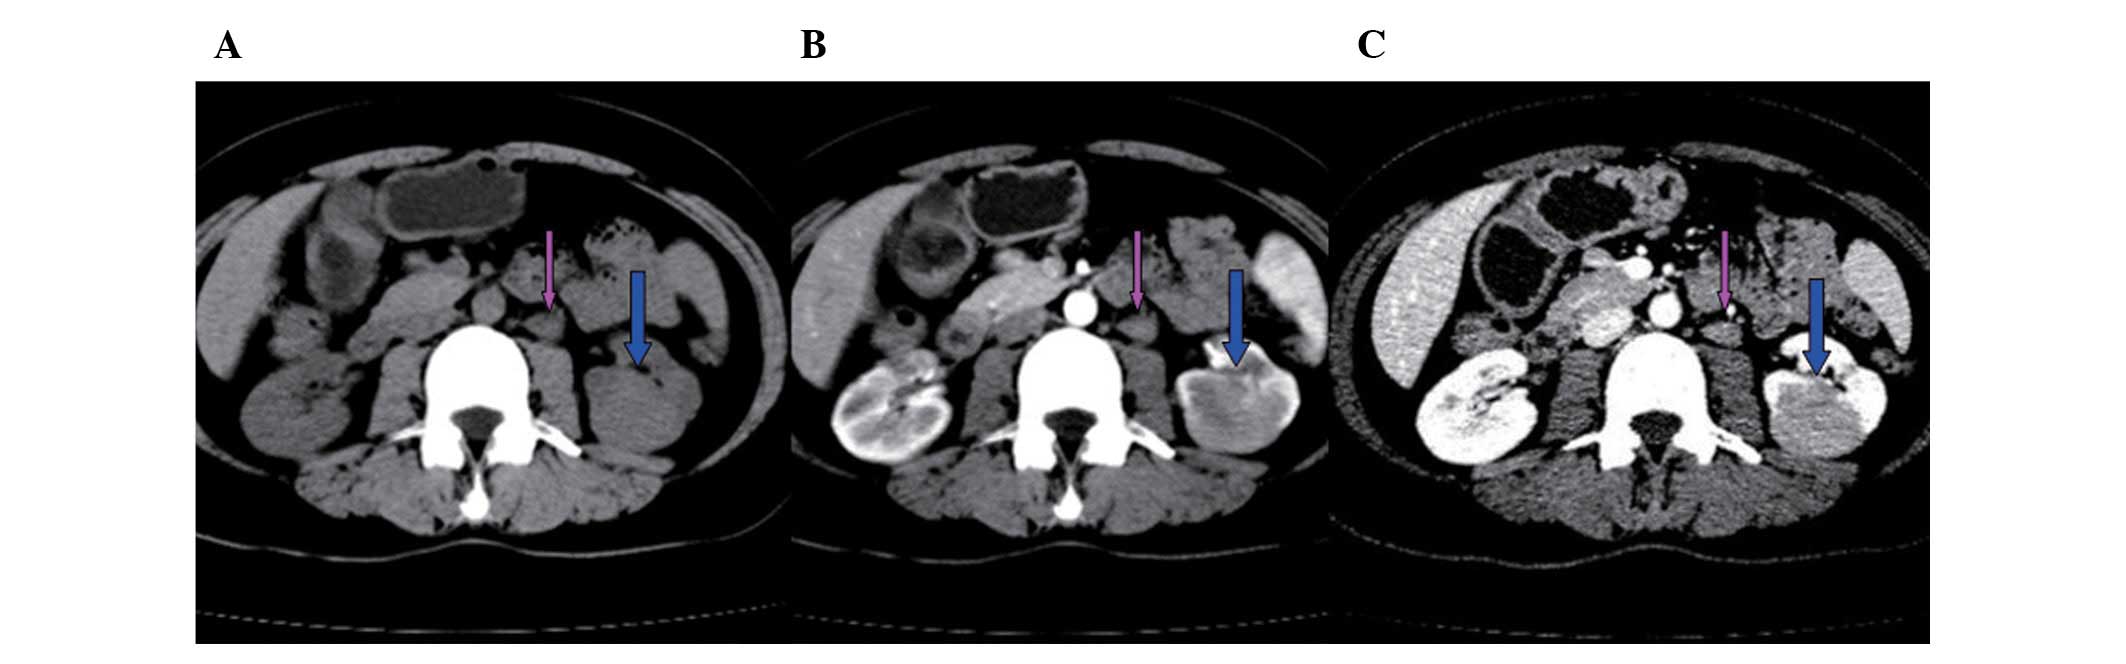

A mass in the left kidney was detected in a 46-year-old female patient who underwent ultrasonography as part of a routine physical checkup. Computed tomography (CT) revealed that the mass showed enhancement, was located in the lower pole of the left kidney and measured 38×30 mm. Furthermore, metastasis was detected in an enlarged (20 mm) para-aortic lymph node (Fig. 1). The radiologist suspected a diagnosis of renal cell carcinoma and advised a partial nephrectomy. However, the pre-operative work-up revealed the following: white blood cell (WBC) count, 2.7×109/l; percentage of neutrophils (NE%), 61.8; red blood cell (RBC) count, 3.58×1012/l; hemoglobin (HGB) level, 101.1 g/l; platelet (PLT) count, 187.6×109/l; and serum creatinine, calcium and phosphorus levels within normal ranges.

Figure 1

CT scans reveal that the mass (blue arrow) showed enhancement, was located in the lower pole of the left kidney and measured 38×30 mm. Metastasis was detected in an enlarged (20 mm) para-aortic lymph node (pink arrow). CT values; (A) plain scan, 40–60; (B) arterial phase, 71–89; (C) venous phase, 90–120. CT, computed tomography.